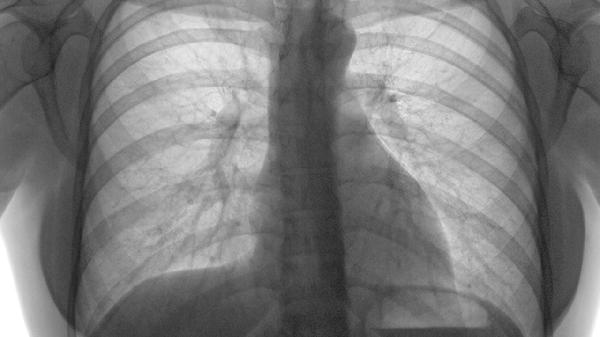

肋骨骨折一般會持續(xù)疼痛1-3個月,具體時間與骨折嚴重程度、個人體質(zhì)及護理措施有關(guān)。

單純性肋骨骨折未合并內(nèi)臟損傷時,疼痛通常在1-2周內(nèi)達到高峰,隨后逐漸緩解。骨折部位會伴隨呼吸、咳嗽或體位變動出現(xiàn)刺痛感,此時需避免劇烈活動,可通過胸帶固定減輕移動性疼痛。疼痛緩解初期可能持續(xù)2-4周,期間骨痂開始形成,但局部仍存在鈍痛或酸脹感。多數(shù)患者在4-6周后疼痛明顯減輕,日?;顒踊静皇芟蓿耆謴托?-12周。若骨折端移位不明顯且未傷及胸膜,疼痛程度較輕,恢復時間可能縮短至3-6周。

合并多根肋骨骨折或開放性骨折時,疼痛周期可能延長至3個月以上。嚴重損傷可能伴隨肋間神經(jīng)受壓或胸膜刺激,導致持續(xù)性灼痛或放射痛,需配合鎮(zhèn)痛藥物干預。老年患者或存在基礎(chǔ)疾病者因愈合速度較慢,疼痛持續(xù)時間可能超過常規(guī)周期。若出現(xiàn)延遲愈合或感染,疼痛可能反復發(fā)作,需通過影像學檢查評估恢復情況。